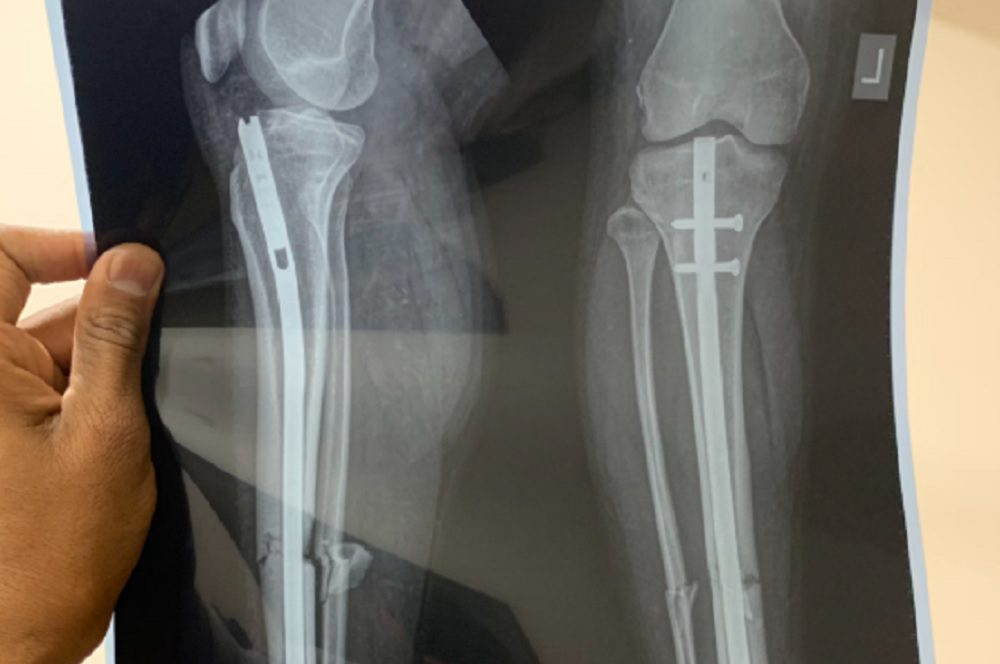

Chấn thương xương, đặc biệt gãy xương nặng, từ lâu là một thách thức đối với các bác sĩ phẫu thuật chỉnh hình. Các phương pháp truyền thống để điều trị những loại chấn thương này thường dựa vào những vật liệu cấy ghép được chế tạo sẵn, chẳng hạn như tấm kim loại, ghép xương từ người hiến tặng hoặc vật liệu in 3D.

Tuy nhiên, các giải pháp này có nguy cơ dẫn đến nhiều vấn đề đối với các vết gãy xương bất thường hoặc phức tạp. Các vật liệu cấy ghép phải được thiết kế và sản xuất riêng trước khi phẫu thuật, một quá trình vô cùng tốn thời gian và vẫn có thể không vừa khít hoàn hảo.